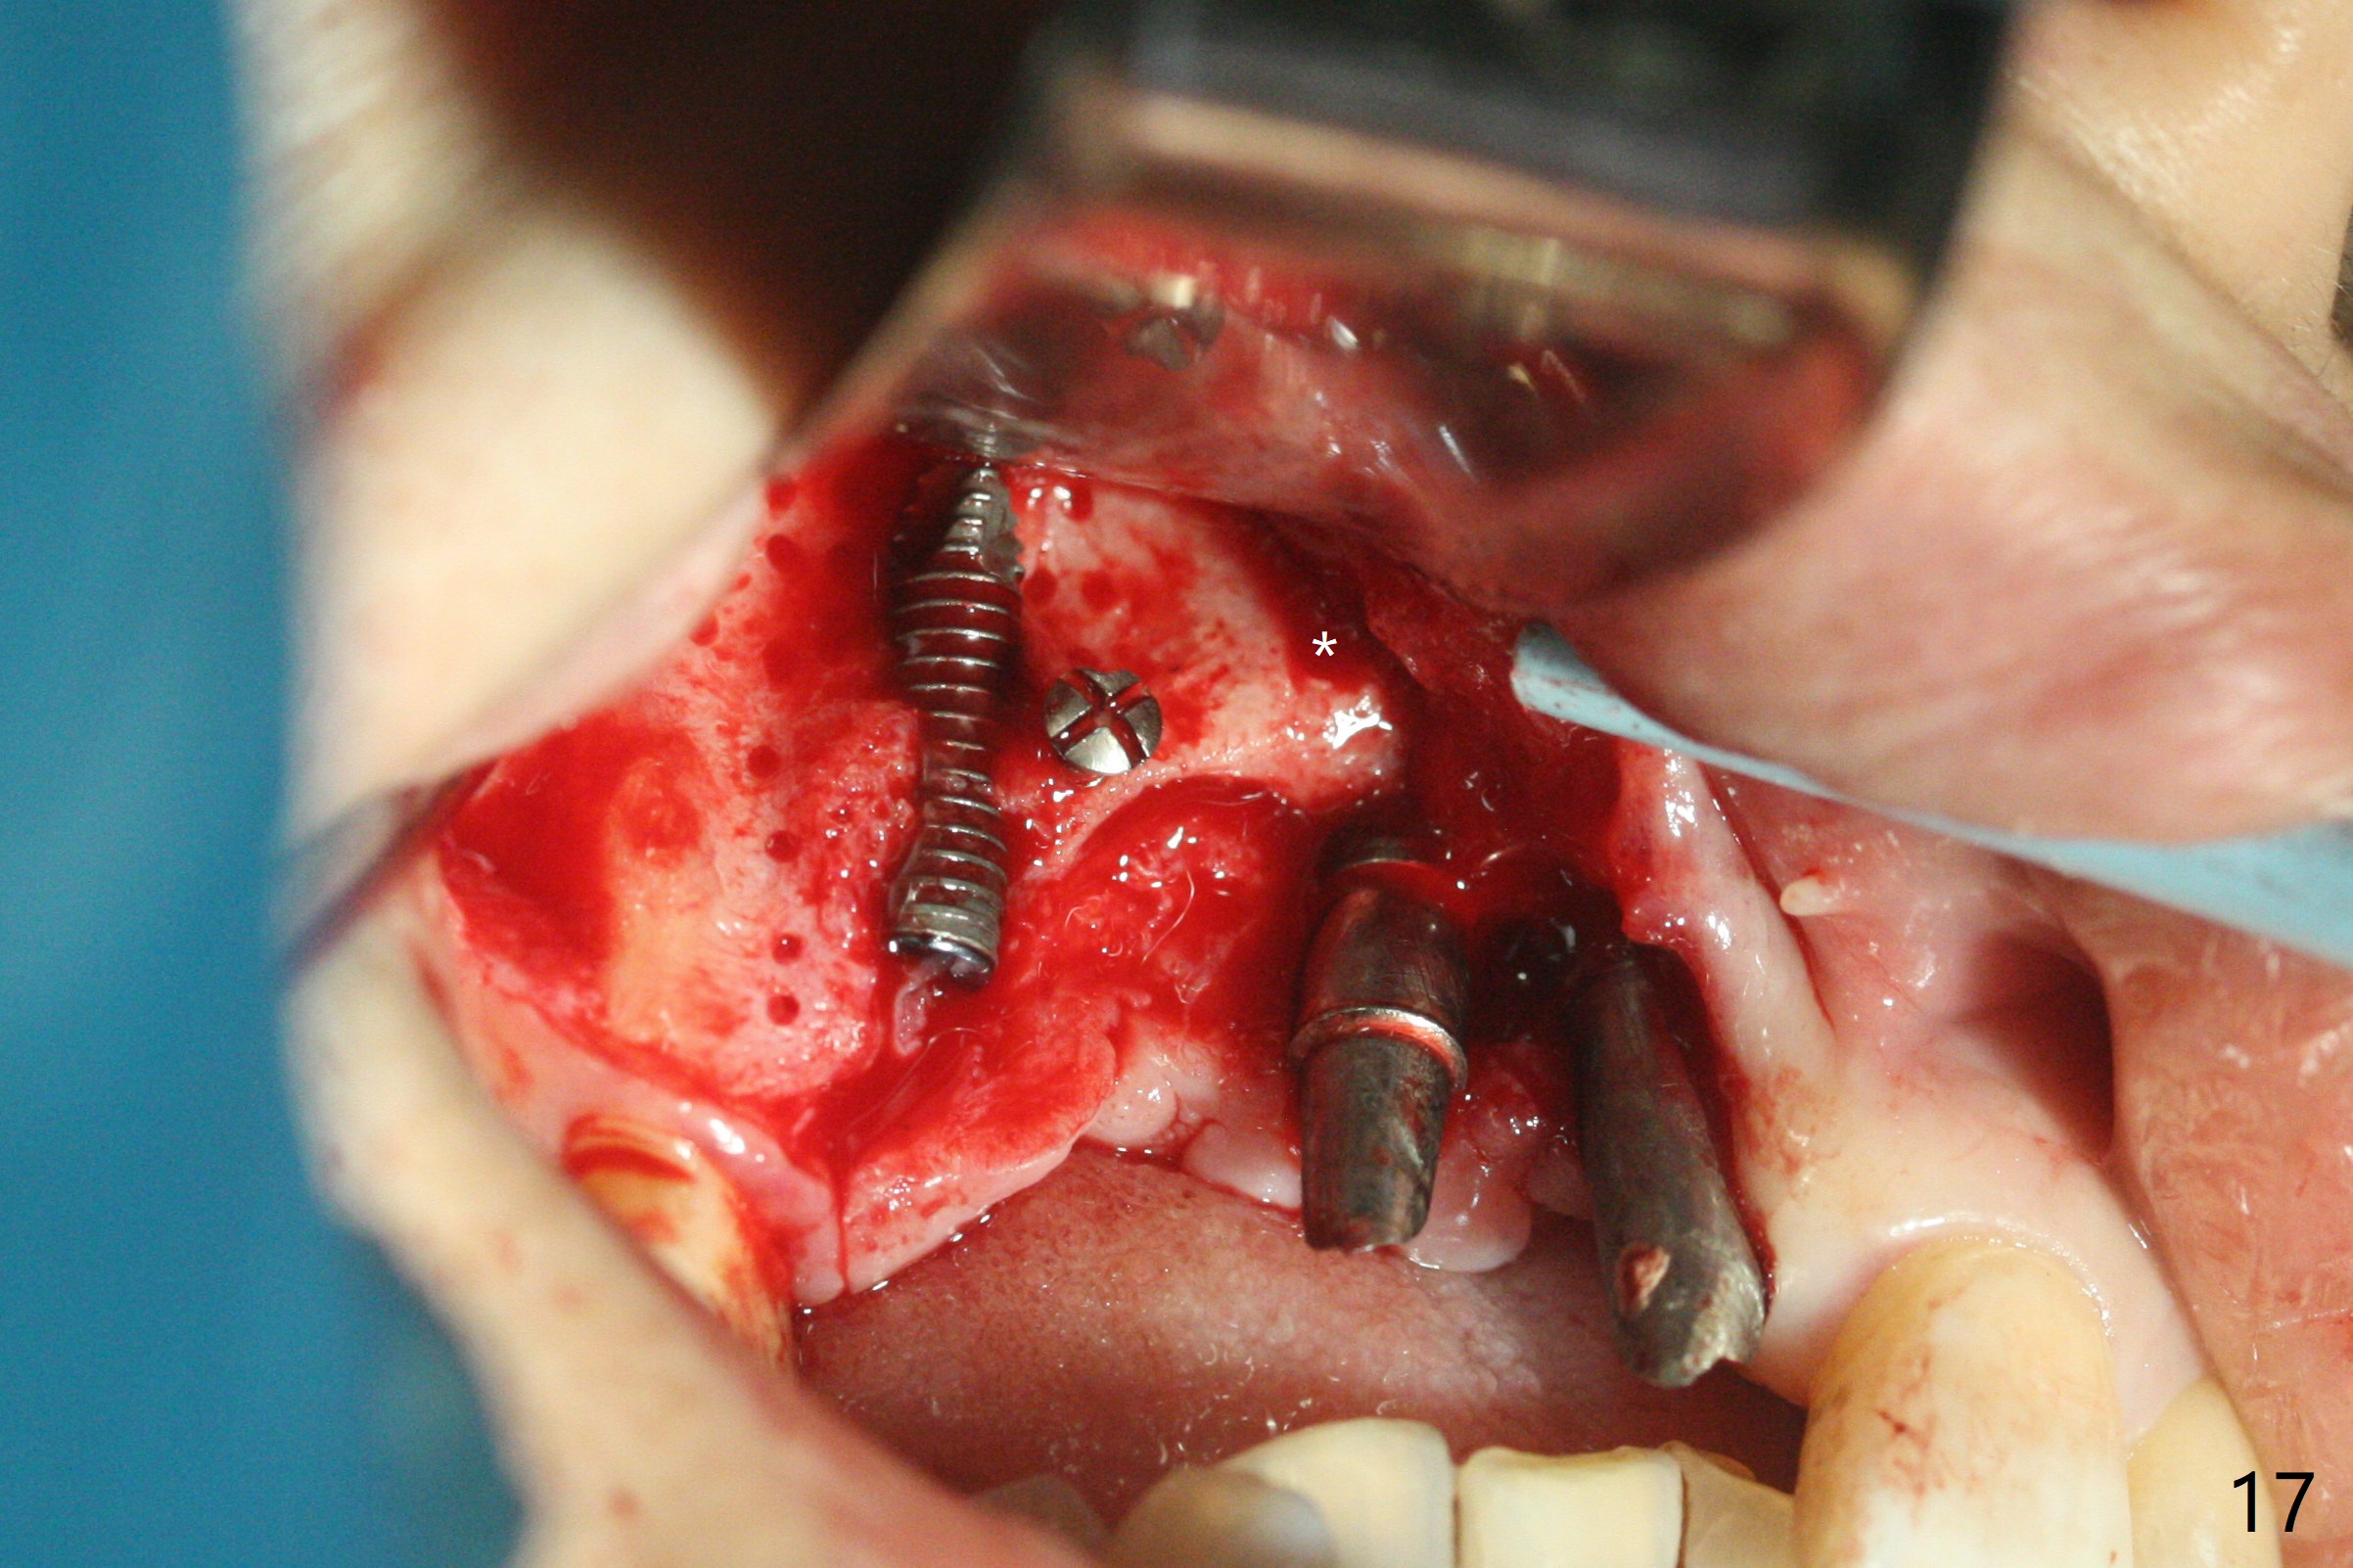

在6,7号牙位牙槽嵴切口,翻瓣,找不到上次放置的tenting screw,不过7号牙位骨质虽然低,够宽的,开始钻洞(图四),植入3.8乘8.5毫米植体,扭力足够(图五),近中舌侧暴露螺纹堆加骨粉(图五*),然后放置基台,再次在后者周围放置骨粉(图五至七),覆盖两张PRF膜后缝合(图八),最后在三个箭头周围放置牙周敷料。术后CT显示植体与tenting screws(图九,十箭头)有一定距离,但是5号牙植体颊侧根尖穿孔(图九 *)。如果植体不脱落,需做侧方切口植骨。术后七天7号植体腭侧肿胀(图十一 *),切开没有脓水,插入牙胶尖,它末端指向7号植体周围tenting screw。后者可能需要拔除,同时5号牙颊侧根尖植骨,但是为时太早,可能打搅骨粉生长。术后两周腭侧肿胀没有消失,但是不痛,继续观察。术后接近6个月,软组织正常(图十三),但是5,7植体周围没有骨质(图十四,五)。由于近中tenting screws周围软组织触痛(局麻不全情况下),螺钉取出(图十六,七(*)),而远中螺钉好像有帮助5植体螺纹骨粉撑起,所以留下(腭侧穿孔部分去除),最后放置粘性骨粉(图十八:*)和PRF膜(两张由7基台打孔固定)。